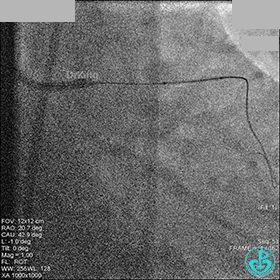

1周后再次上台,右冠脉3级血流,3段局限性严重狭窄,内膜模糊,应该是上次操作夹层遗留下的血肿。